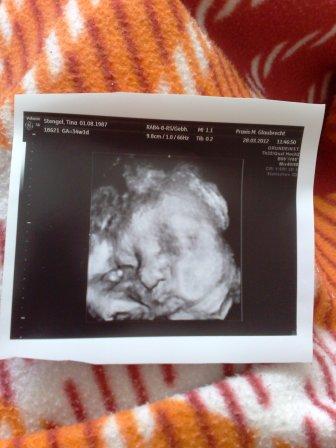

Ich war gestern (34+1) wieder zur VU und meine Gyn hat zum 1. Mal 3 D geschallt und da meine Püppi so toll lag, konnte man ihr süßes Gesichtchen sehen, sie sieht so knuffig aus Vielleicht könnt ihr ja auch was erkennen

Bild zu